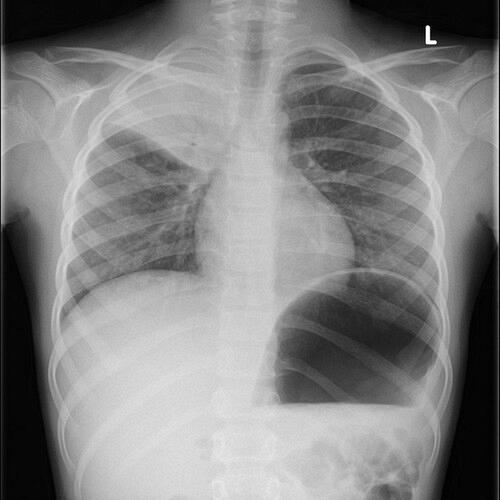

De laboratoriumbepalingen bezinking (bezinkingssnelheid erytrocyten, BSE), het C-reactieve proteïne (CRP) en de leukocyten worden in de kliniek veelvuldig aangevraagd ter analyse van een onderliggende ziekte of worden serieel gemeten bij het vervolgen van een ziekte. Hoe deze bepalingen geïnterpreteerd dienen te worden, wordt geïllustreerd aan de hand van een casus.